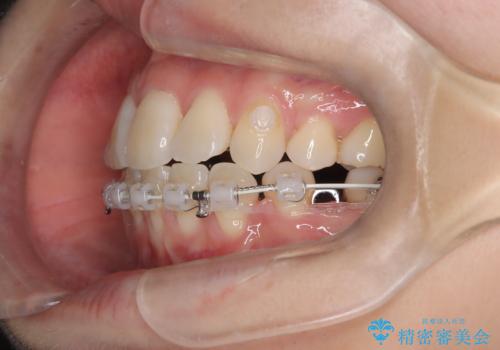

- 患者様は下顎の前歯が3本しかないという特異な歯列を持ち、噛み合わせのバランスが崩れていました。上下の歯の本数が通常と異なるため、抜歯部位の選定が重要となるケースでした。診査の結果、歯の位置や咬合のバランスを考慮し、上顎の両側小臼歯2本と左下の小臼歯1本を抜歯することで、上下の噛み合わせを整える方針としました。矯正装置は、**目立ちにくいハーフリンガル(上顎は裏側矯正・下顎は表側矯正)**を採用しました。

まず、計画通りに抜歯を行い、歯列のスペースを確保しました。上顎は裏側矯正(リンガル)で目立たないように配慮しながら歯を後方へ移動し、下顎は表側矯正を使用して、3本の前歯の位置関係を調整。上下の歯の噛み合わせを細かくコントロールしながら、全体のバランスを整えました。治療後は「歯並びがきれいになり、噛み合わせもしっかり合うようになった」と患者様にも満足していただけました。